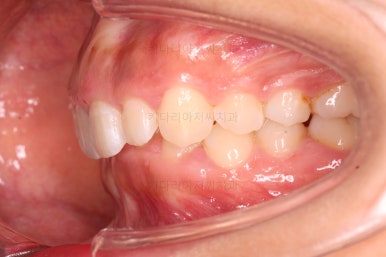

오늘 소개해 드릴 환자분은 아래 앞니가 하나 없는 결손치아, 그로 인해서 윗니 앞니가 뒤로 굽어 들어오는 "옥니", 그로 인해 위아래 앞니가 많이 겹치는 과개교합 및 잇몸웃음(거미스마일)이 나타나는 복합적인 문제가 있는 분이셨습니다.

옆라인에서 입은 튀어나온 느낌은 없지만 턱끝만 살짝 볼륨감이 있는 편이었어요.

그렇다고 주걱턱은 아닙니다.